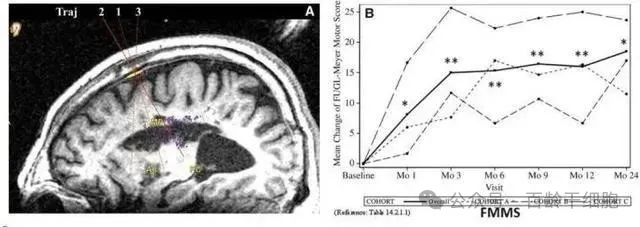

2019年,我国某医院在《干细胞转化医学》杂志上公布了一项令人振奋的研究成果。他们发现,干细胞回输有助于脑卒中偏瘫患者运动功能的恢复。在这项临床研究中,9名年龄在30至65岁之间的偏瘫患者接受了干细胞的脑内回输。这些患者在中风后5-24个月接受了治疗,干细胞被精确地回输至脑内梗塞灶附近。

影像学研究的结果令人振奋,干细胞输入区出现了新的神经组织,这证明了干细胞干预偏瘫性脑卒中具有一定的临床益处。通过24个月的随访,临床结果显示,相对于基线,患者的分数发生了显著变化,9例患者的影像学显示病变区域的组织都发生了明显变化。

图片

这项研究的成功在于,回输到脑内梗塞病灶的干细胞能够分化为神经系统的各类细胞,并分泌营养因子。这些因子促进了神经和血管的再生,修复了受损的血-脑脊液屏障,并减轻了炎性反应。这一系列的作用共同促进了脑梗死动物的神经功能恢复,使得9例临床患者的偏瘫症状得到了明显改善。